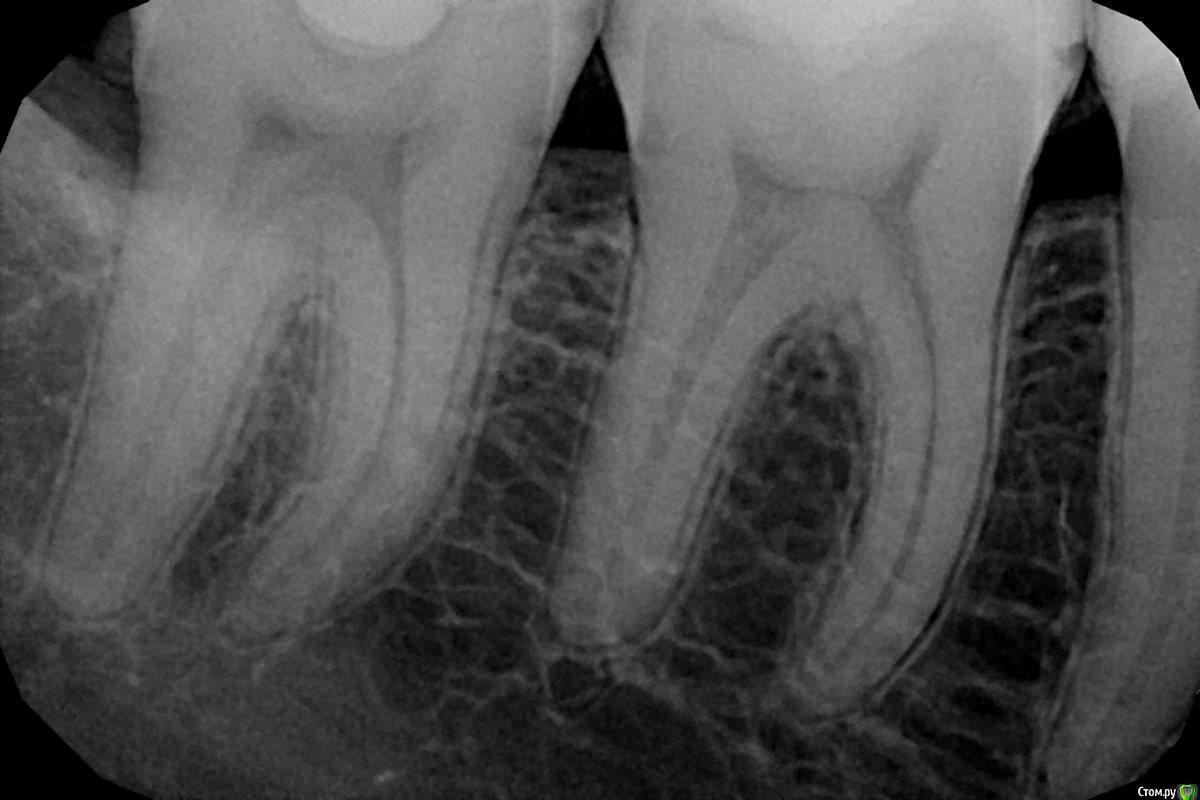

aleksandrovna_o Опубликовано 1 октября, 2020 Поделиться Опубликовано 1 октября, 2020 Здравствуйте, уважаемые врачи. Решила перестраховаться.Доктор, посмотрев на прицельные снимки, сказала, что есть кариес в двух местах. Один - его прямо срочно-срочно надо лечить, а другой - можно подождать максимум пол года. НО, у меня вообще там ничего не болит, нет реакции на горячее холодное, когда ем. Это как? такое разве бывает? посмотрите, пожалуйста, на снимки и скажите, действительно ли срочно нужно лечить.Первые два снимка - зубы 46-47. Там, если не ошибаюсь, кариес между зубами.Третий снимок — зубы 15,16,17.Буду очень признательна. Ссылка на комментарий

St. Опубликовано 1 октября, 2020 Поделиться Опубликовано 1 октября, 2020 Когда уже болит и чувствуется - разрушение глубокое. Лучше полечить на более ранней стадии это лучше в прогнозе , быстрее и дешевле Ссылка на комментарий